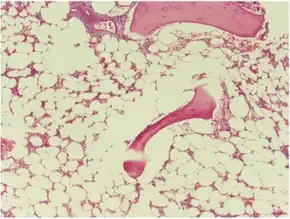

Micrograph of bone marrow taken from a person with aplastic anemia. The bone marrow is mostly fat cells with few blood forming cells.[2] | |

The cause is unclear in 65% of cases.[3] Other cases may occur following a viral infections, due to a genetic conditions such as Fanconi anemia, or exposure to chemicals, medications or radiation.[3][4] The diagnosis may be suspected based on low blood cells together with low reticulocytes and the absence of changes concerning for blood cancer.[3] The diagnosis is confirmed by a bone marrow biopsy finding mostly fat cells instead of blood forming cells.[5]